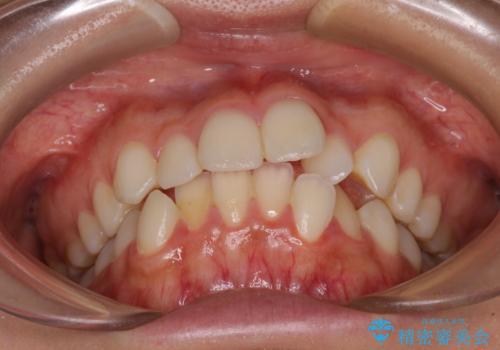

- 前歯のデコボコとクロスバイトを気にして来院された患者様です。

上顎側切歯(上の真ん中から2番目の歯)が舌側転位している場合、インビザラインでは仕上げきれないことが多く、更には無理して動かそうとすると歯髄壊死を起こすリスクが高いと言われています。

今回は、ワイヤー装置を併用することなく、インビザライン単体で矯正治療を行うこととしました。